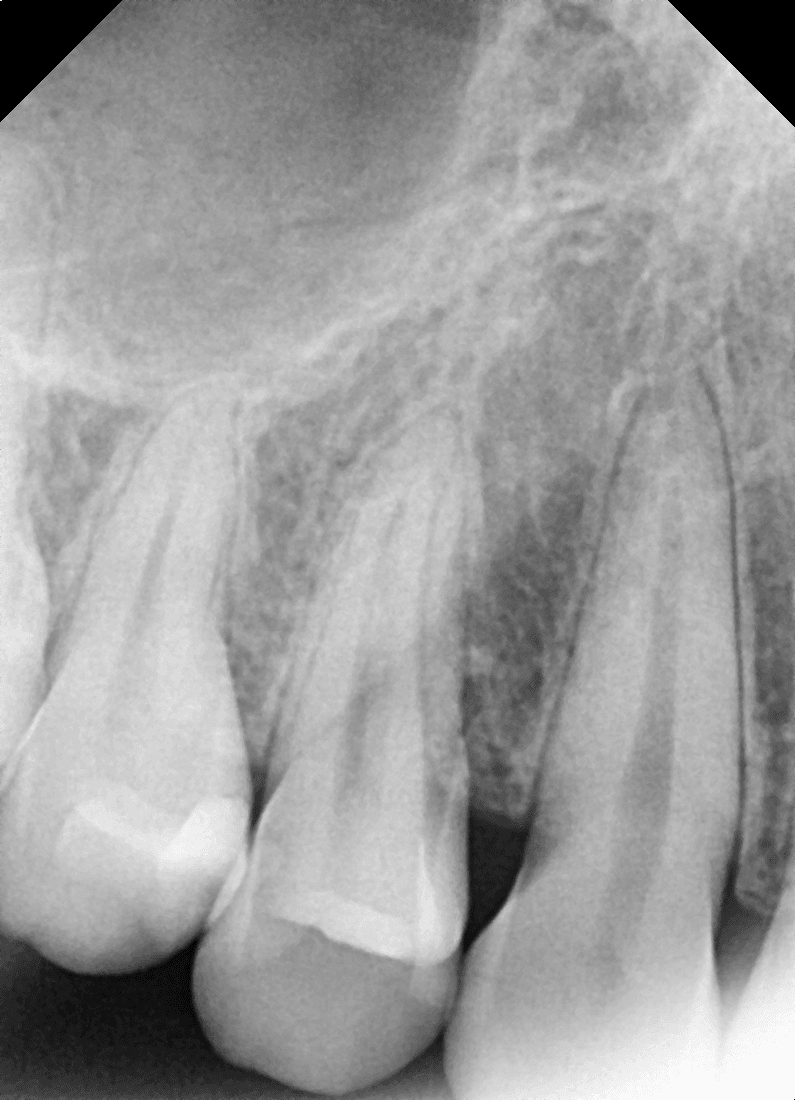

부분틀니 가격은 200~300만원 사이로써 꼈다 뺐다하는 것 의치뿐만 아니라 걸어줄 수 있는 지대치도 필요합니다.

틀니는 잇몸 위에 얹어 사용하는 보철물이기 때문에, 미세한 높낮이나 압력 차이만 있어도 특정 부위에 지속적인 자극이 가해질 수 있습니다.